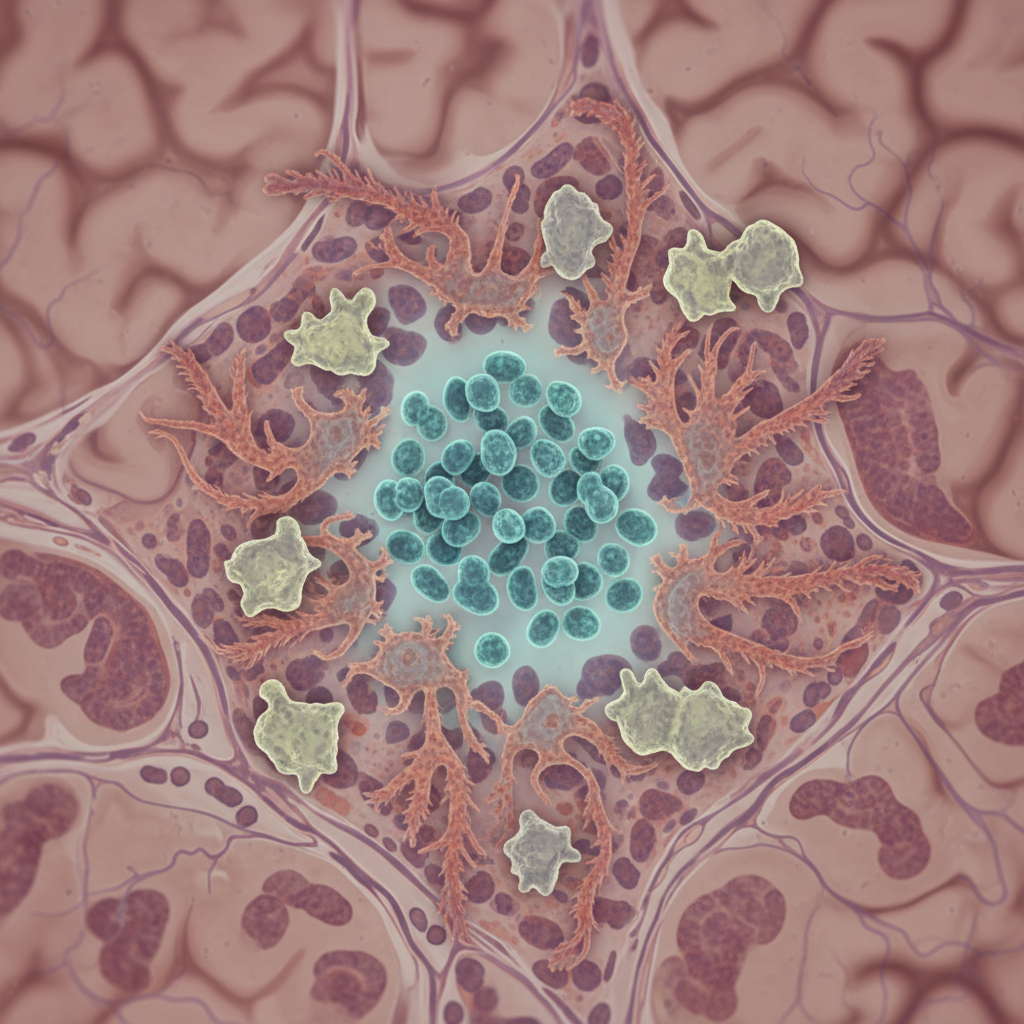

La inflamación crónica podría dejar huellas duraderas en células madre del intestino y ayudar a explicar un mayor riesgo de cáncer colorrectal, pero la evidencia disponible aquí no basta para confirmarlo

La inflamación crónica podría dejar huellas duraderas en células madre del intestino y ayudar a explicar un mayor riesgo de cáncer colorrectal, pero la evidencia disponible aquí no basta para confirmarlo Pocas ideas son tan importantes en la biología...